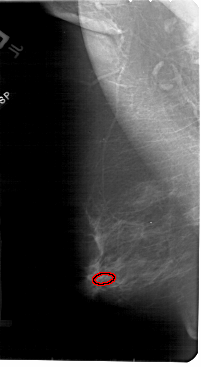

A_1840_1.LEFT_CC

FILE: A_1840_1.LEFT_CC.OVERLAY

TOTAL_ABNORMALITIES 1

ABNORMALITY 1

LESION_TYPE CALCIFICATION TYPE PLEOMORPHIC DISTRIBUTION CLUSTERED

ASSESSMENT 4

SUBTLETY 2

PATHOLOGY BENIGN

TOTAL_OUTLINES 1

BOUNDARY